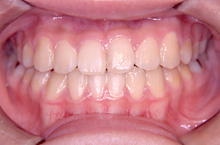

常滑市井戸田町在住 S.M様(23歳女性)

S.M様は口元の突出感と上顎前歯の傾きを主訴に当院の無料矯正相談にて来院されました。

来院当初より当院にて矯正治療をご希望されましたので通常通り模型採取、レントゲン撮影、口腔内写真の撮影、

正貌・側貌の撮影などの試料採取を行いました。

診断の結果、咬み合わせが骨格的には反対咬合傾向の上下顎前突である事や前歯上顎前歯の歯軸が左右方向に流れて傾斜していること、

咬み合わせが浅いことなど治療はやや難度の高いことをお話しいたしました。

前歯の咬み合わせが浅く切端咬合です。上顎前歯の歯軸が左右的に傾いています。

犬歯関係・臼歯関係ともにClass3です。

![]() |

犬歯関係、臼歯関係を咬み合わせが1歯対2歯のClass1に治療するためと口元の突出感を改善するために右側は上下顎第1小臼歯を抜歯しました。

左側は上顎第2小臼歯、下顎第1小臼歯を抜歯しました。

治療の経過で一時、反対咬合傾向がでましたが処置方針通り治療がすすみました。

S.M様は一度のキャンセルもなく予定通り来院治療され、

お渡ししてあった治療計画書通りに2年6ヶ月(30ヶ月)で動的治療を終えることができました。

治療期間:2年6ヶ月

治療費用:60万円